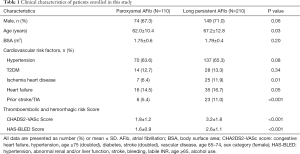

Detailed clinical baseline characteristics are shown in Table 1. Our retrospective study enrolled 330 symptomatic AFib patients who were anti-arrhythmic drugs resistant and required cardioversion or radiofrequency ablation. Among them, 110 patients were paroxysmal AFib, and 220 were long-standing AFib patients. There were 149 (71.0%) male patients in the long-standing AFib group, and 76 (69.1%) male patients in the paroxysmal AFib group. In the paroxysmal AFib group, the mean age was 62.0±10.4 years, and the body surface area was 1.75±0.6 m2. The mean age and body surface area in long-standing AFib group was 67.2±12.8 years and 1.79±0.4 m2, respectively. We used CHA2DS2-VASc and HAS-BLED scoring system to assess the risk factors. The long-standing AFib group patients had high grade of thromboembolic (CHA2DS2-VASc =3.2±1.8) and hemorrhagic risk (HAS-BLED =2.6±1.1), whereas paroxysmal AFib group patients had moderate thromboembolic and hemorrhagic risk (1.8±1.2 and 1.6±0.9, respectively). Hypertension, diabetes, ischemia heart disease, congestive heart failure (CHF), and prior stroke/TIA were present in 70 (63.6%), 14 (12.7%), 7 (6.4%), 16 (14.5%), and 6 (5.4%) paroxysmal AFib patients, compared with 137 (65.3%), 28 (13.3%), 25 (11.9%), 35 (16.7%), and 23 (11.0%) long-standing AFib patients. The incidences of ischemia heart disease and stroke were statistically significant between the two groups, whereas there was no statistically significant difference in the incidence of hypertension, T2DM, and heart failure (Table 1).

Full table